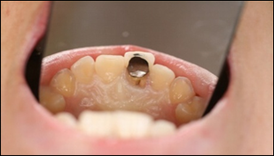

術前口腔内写真術前口腔内写真

歯が割れて唇側に傾いています。

仮歯をつけるための土台です。

手術当日の仮歯です。